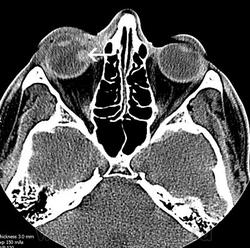

Орбитальная патология. Гематома. +

Гематома стекловидного тела.